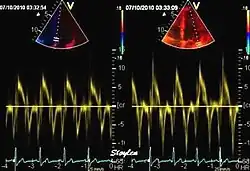

During the two filling phases, there is early (E) and late (A) blood flow from the atrium to the ventricle, corresponding to the annular velocity phases. The flow, is driven by the pressure difference between atrium and ventricle, this pressure difference is both a function of the pressure drop during early relaxation and the initial atrial pressure. In light diastolic dysfunction, the peak early mitral flow velocity E is reduced in proportion to the e', but if relaxation is so reduced that it causes increase in atrial pressure, E will increase again, while e', being less load dependent, remains low. Thus, the ratio E/e' is related to the atrial pressure, and can show increased filling pressure[15][16] although with several reservations.[17][18] In the right ventricle this is not an important principle, as the right atrial pressure is the same as central venous pressure which can easily be assessed from venous congestion.[19][20]

relation between mitral flow and mitral annulus velocity. Left: Normal person with good diastolic function; high E and e', normal E/e'. Middle, patient with diastolic dysfunction without increased filling pressure; low E and e', normal E/e' ratio. Left, patient with diastolic dysfunction and increased filling pressure; high E, low e' and high E/e'. The S' is reduced in proportion to the e'